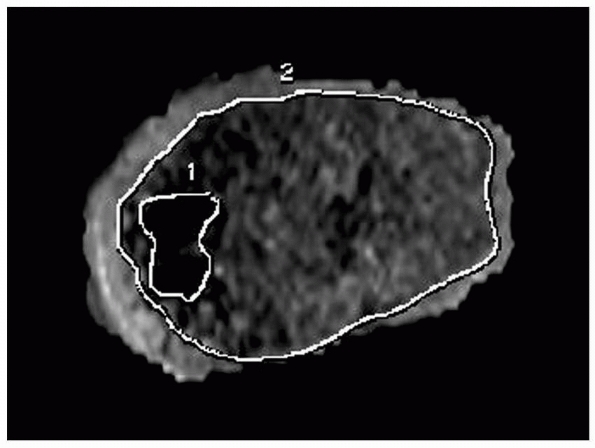

the rest of the physis must be carefully documented. The most

cost-effective method to accurately evaluate an arrest is with

reconstructed sagittal and coronal CT images to provide views

orthogonal to the affected physis. MRI may also be used and, with

recent

advancements in the capability to identify and quantify physeal

arrests, may soon become the imaging study of choice. We currently

prefer three-dimensional spoiled recalled gradient echo images with fat

saturation or fast spin echo proton density images with fat saturation

to visualize the physis. CT images allow precise delineation of bony

margins and, at the current time, is cheaper than MRI. An estimation of

the affected surface area can be computed with the assistance of the

radiologist using a modification of the method of Carlson and Wenger (Fig. 5-40).35 The procedure should be planned with consideration of the principles discussed in the following section.

| Figure 5-40 Reconstructed MRIs allow estimation of the percentage of surface area of the physis affected by a growth arrest. This workstation reconstruction delineates the perimeter of normal physis (border 2) and that of the physeal arrest (border 1). Surface area affected can be calculated from these reconstructions. |